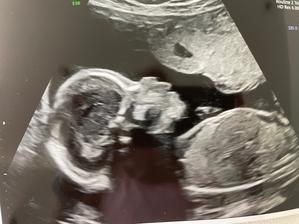

Tyden po kontrole 14.1.2022 jsem našla dvě carky na testu. Byl to docela šok, vzhledem ke štítné zlaze a 4,5 letech neúspěchů. Dvě carky stále sili, ale strach je veliký.